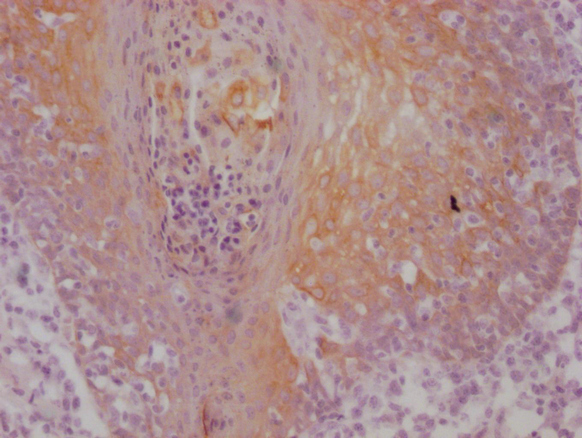

IHC image of CSB-MA898464 diluted at 1:100 and staining in paraffin-embedded human tonsil tissue performed on a Leica BondTM system. After dewaxing and hydration, antigen retrieval was mediated by high pressure in a citrate buffer (pH 6.0). Section was blocked with 10% normal goat serum 30min at RT. Then primary antibody (1% BSA) was incubated at 4°C overnight. The primary is detected by a Goat anti-mouse IgG polymer labeled by HRP and visualized using 0.05% DAB.